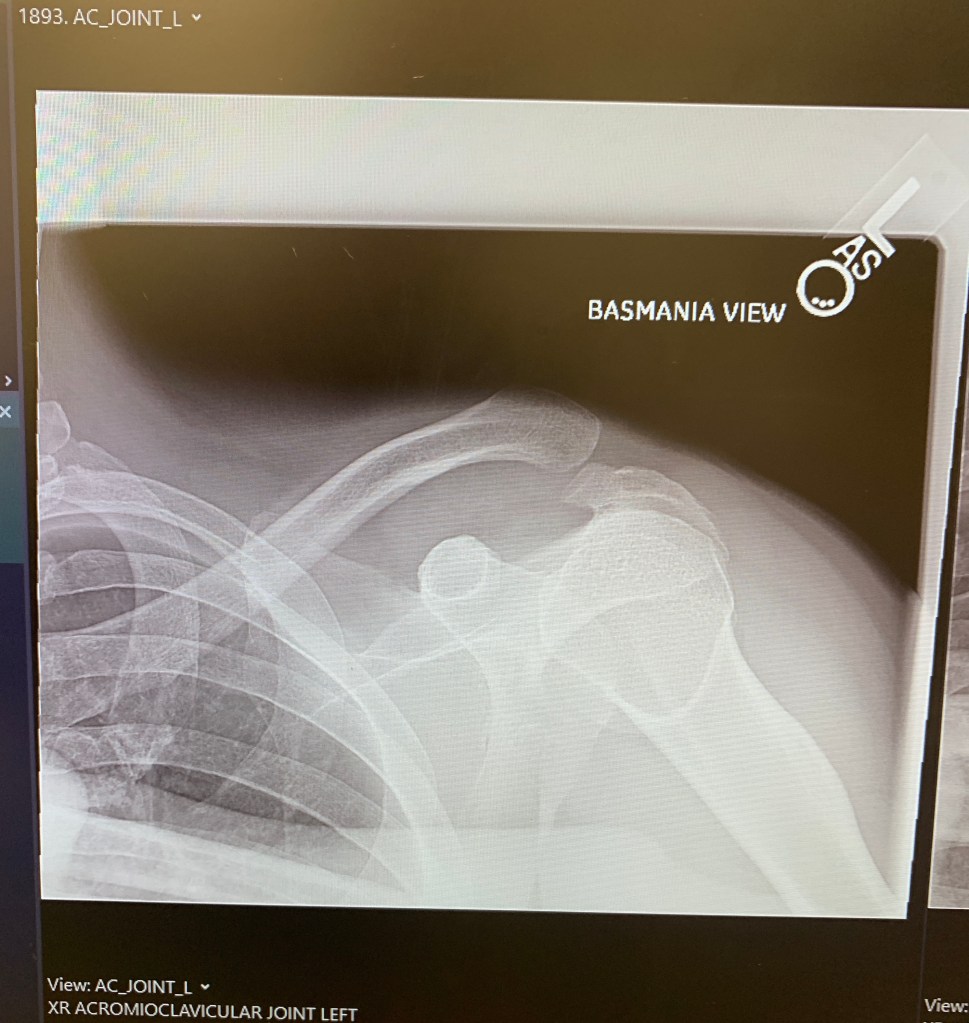

And, of course, he wanted to provide an update for interested readers: The update: don't panic (yet). As you can see vy the X-ray image above, Kuntzman's clavicle (jambiuolum Tiberius in Latin, or so he claims) has separated from the arm bone, though to the layman's eye (his), it appears to have come in completely shorn off. Apparently, Kuntzman will need special surgery, conveniently enough, at the Hospital for Special Surgery, that and he is not making this up, will require a doctor to take the Achilles tendon of a cadaver, screw it into the clavicle, and sew the overhanging tendon (or ligament, we always mix those up) to the torn tendon (or cartilage, we always mix that up, too) and tie that clavicle back into place.